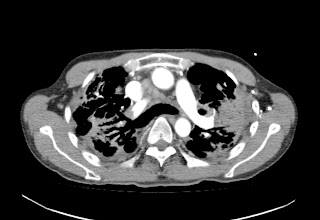

Hombre de 61 años asintomático. Colonoscopia demuestra válvula ileocecal ulcerada y estenótica. No hay antecedente de Enfermedad Inflamatoria Intestinal.

Con base en lo anterior el siguiente paso a seguir es?

a) Valoración por cirugía general.

b) Iniciar tratamiento con anti-inflamatorios e inmunosupresores.

c) Biopsia bajo guía ecográfica de las lesiones focales hepáticas.

d) Repetir colonoscopia.